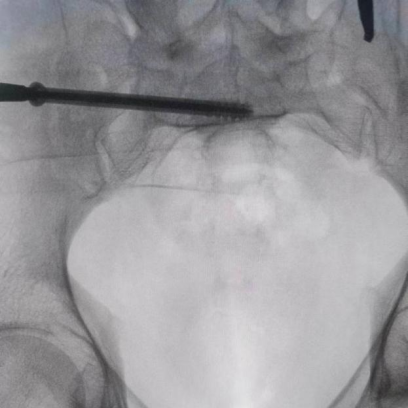

據(jù)了解,患者37歲,為高墜傷患者,入院合并顱腦挫傷、盆腔臟器出血、骨盆骨折多發(fā)傷患者。為最大限度降低手術(shù)風(fēng)險(xiǎn),同時(shí)給予患者滿意的手術(shù)療效,術(shù)前綜合評(píng)估患者病情,擬定行“天璣機(jī)器人”輔助定位下骨盆骨折微創(chuàng)手術(shù)。2月13日10時(shí),手術(shù)正式開始。拉薩市人民醫(yī)院采集患者術(shù)中二維影像,通過骨科手術(shù)機(jī)器人擬定螺釘打入位置方向后,吳宏華主任完成手術(shù)設(shè)計(jì),成功為該患者置入了一顆高難度骶髂螺釘,出血5ml,切口1cm。術(shù)后圖像顯示,螺釘位置及方向完全符合手術(shù)規(guī)劃,沒有一絲偏差,手術(shù)最終獲得圓滿成功。

圖為透視下見置入的骶髂螺釘,位置、長(zhǎng)度精準(zhǔn),無(wú)絲毫偏差